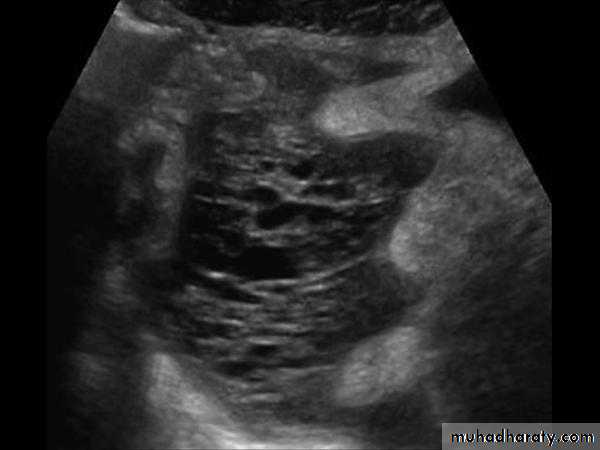

Ascites